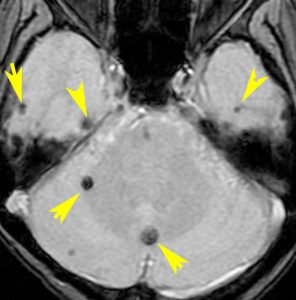

海綿状血管腫 微小血管障害

多発性微小脳出血

- ほとんどが小児に生じるものです

- 放射線治療を受けた患者の40%くらいでみられます

- 照射後10年くらい長期観察をしていると実際に非常に高頻度にみます

- 海綿状血管腫は,放射線誘発2次腫瘍というよりも,放射線による脳内小血管損傷による血管障害として捉えた方がよいです

- T2スターというMRI画像で発見できます

11歳の時に全脳室照射24グレイ・12分割を受けた女の子です。10年以上経過して,脳のあちこちに小さな黒い点状のものが見えるようになってきました。これは子供の頃に放射線治療を受けた人に多く,なんでもないもので症状は出ませんし,ほっておいていいものです。微小な脳静脈の放射線損傷による血液の漏れだと考えられています。

- 低信号(黒いシミみたいなもの)として脳内たくさん見られることがあります

- これは血液の中の鉄分が脳に滲み込んだ形跡をみているものです

- だから,海綿状血管腫とは言わないで,blood leak(血液が漏れた痕跡)と読んだ方がいいものです

- 海綿状血管腫というと腫瘍みたいだからです

- 年月の経過とともに数が増加します

- 海綿状血管腫は発生しても何ら症状を呈することはありません

- 治療をせずに放置します

- まれに小さな脳出血を生じますが,経過を見れば血腫は自然に吸収されます